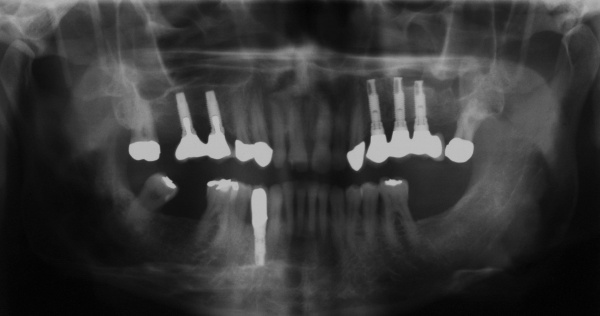

Der Erstbefund vom 20.08.1998 zeigte eine lokalisiert entzündliche marginale Gingiva mit Blutungsneigung auf Sondierung (SBI 32 %) vorrangig in regio 17, 11, 21, 24, 27, 36, 37, 41, 46. Austritt von Pus aus der Tasche an 22. Die Sondiertiefen waren durchweg erhöht, an einzelnen Parodontien konnten bis zu 12 mm sondiert werden (s. Abb. 12). Generalisiert weiche Beläge (API 46 %), harte Beläge in der UK-Front. An 41 singuläre parodontale Rezession und Zahnlockerung des Grades II, hier auch sehr schmale keratinisierte Gingiva. Mobilitätstest und Blanchingtest positiv. Der Röntgenbefund der Panoramaschichtaufnahme vom 11.08.1999 (s. Abb. 13) zeigt einen generalisierten horizontalen Knochenabbau mit vertikalen Einbrüchen in regio 17, 24, 25, 26, 36, 41 und 47. Wurzelfüllung an 36. Konkremente sichtbar. 18 elongiert. 38 und 48 halbretiniert mit Aufhellung distal.